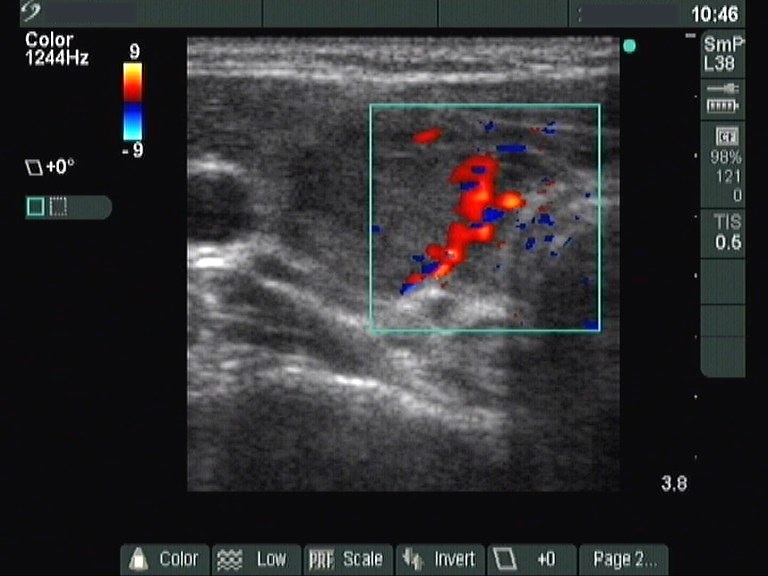

Ultrasonography: revealed hypoechogenic inhomogeneous thyroids. There was a moderately hyperechogenic nodule in the left lobe. The nodule presented a halo sign and perinodular blood flow.